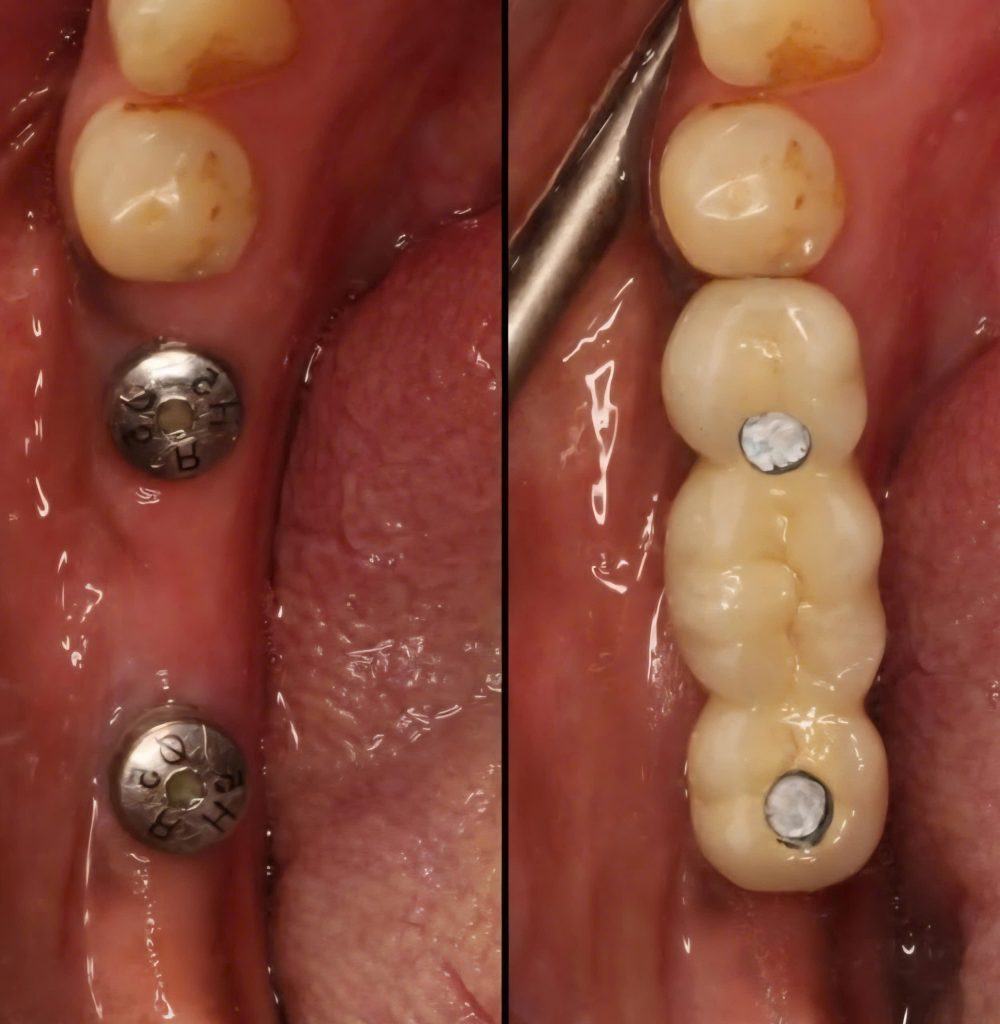

Mất nhiều răng cạnh nhau

Bác sĩ sẽ cấy các Implant chính và tạo cầu răng sứ để tối ưu hoá chi phí mà vẫn đảm bảo chức năng ăn nhai